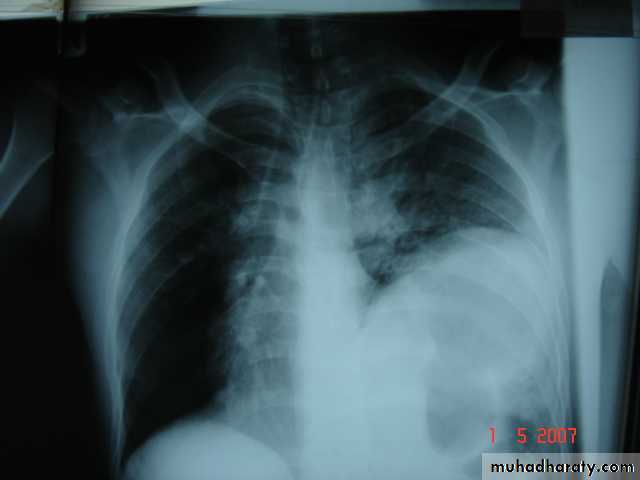

Is the accumulation of air inside the pleural cavity , occurring without any known etiology .More in males ,more on the right side .It can be bilateral

• Causes 1- Ruptured pulmonary bleb.2-Ruptured of a cystic defect in the pleura.3-Teared visceral pleura 4-No cause can be demonstrated in (15-20%).Complications:-1-pleural effusion2-empyema 3-tension pneumothorax which leads to mediastinal shift &circulatory collapse.4-Respiratory failure in elderly patient with COAD .

• 4-Pleural effusion

• Is the accumulation of fluid in the pleural space excessive transudation or exudation of the interstitial fluid from the pleural surface. It is signfrom ify pleural or systemic disease .

• Its effect depends on its size (mild , moderate or massive ) & the state of the underlying lung .It is classified as transudate when the protein content is less than 3g/100ml, or exudates when protein content is more than 3 gm /100ml.Clinically patients will present with dyspnea & pleuritic chest pain

• Radio logically (concave meniscus sign)